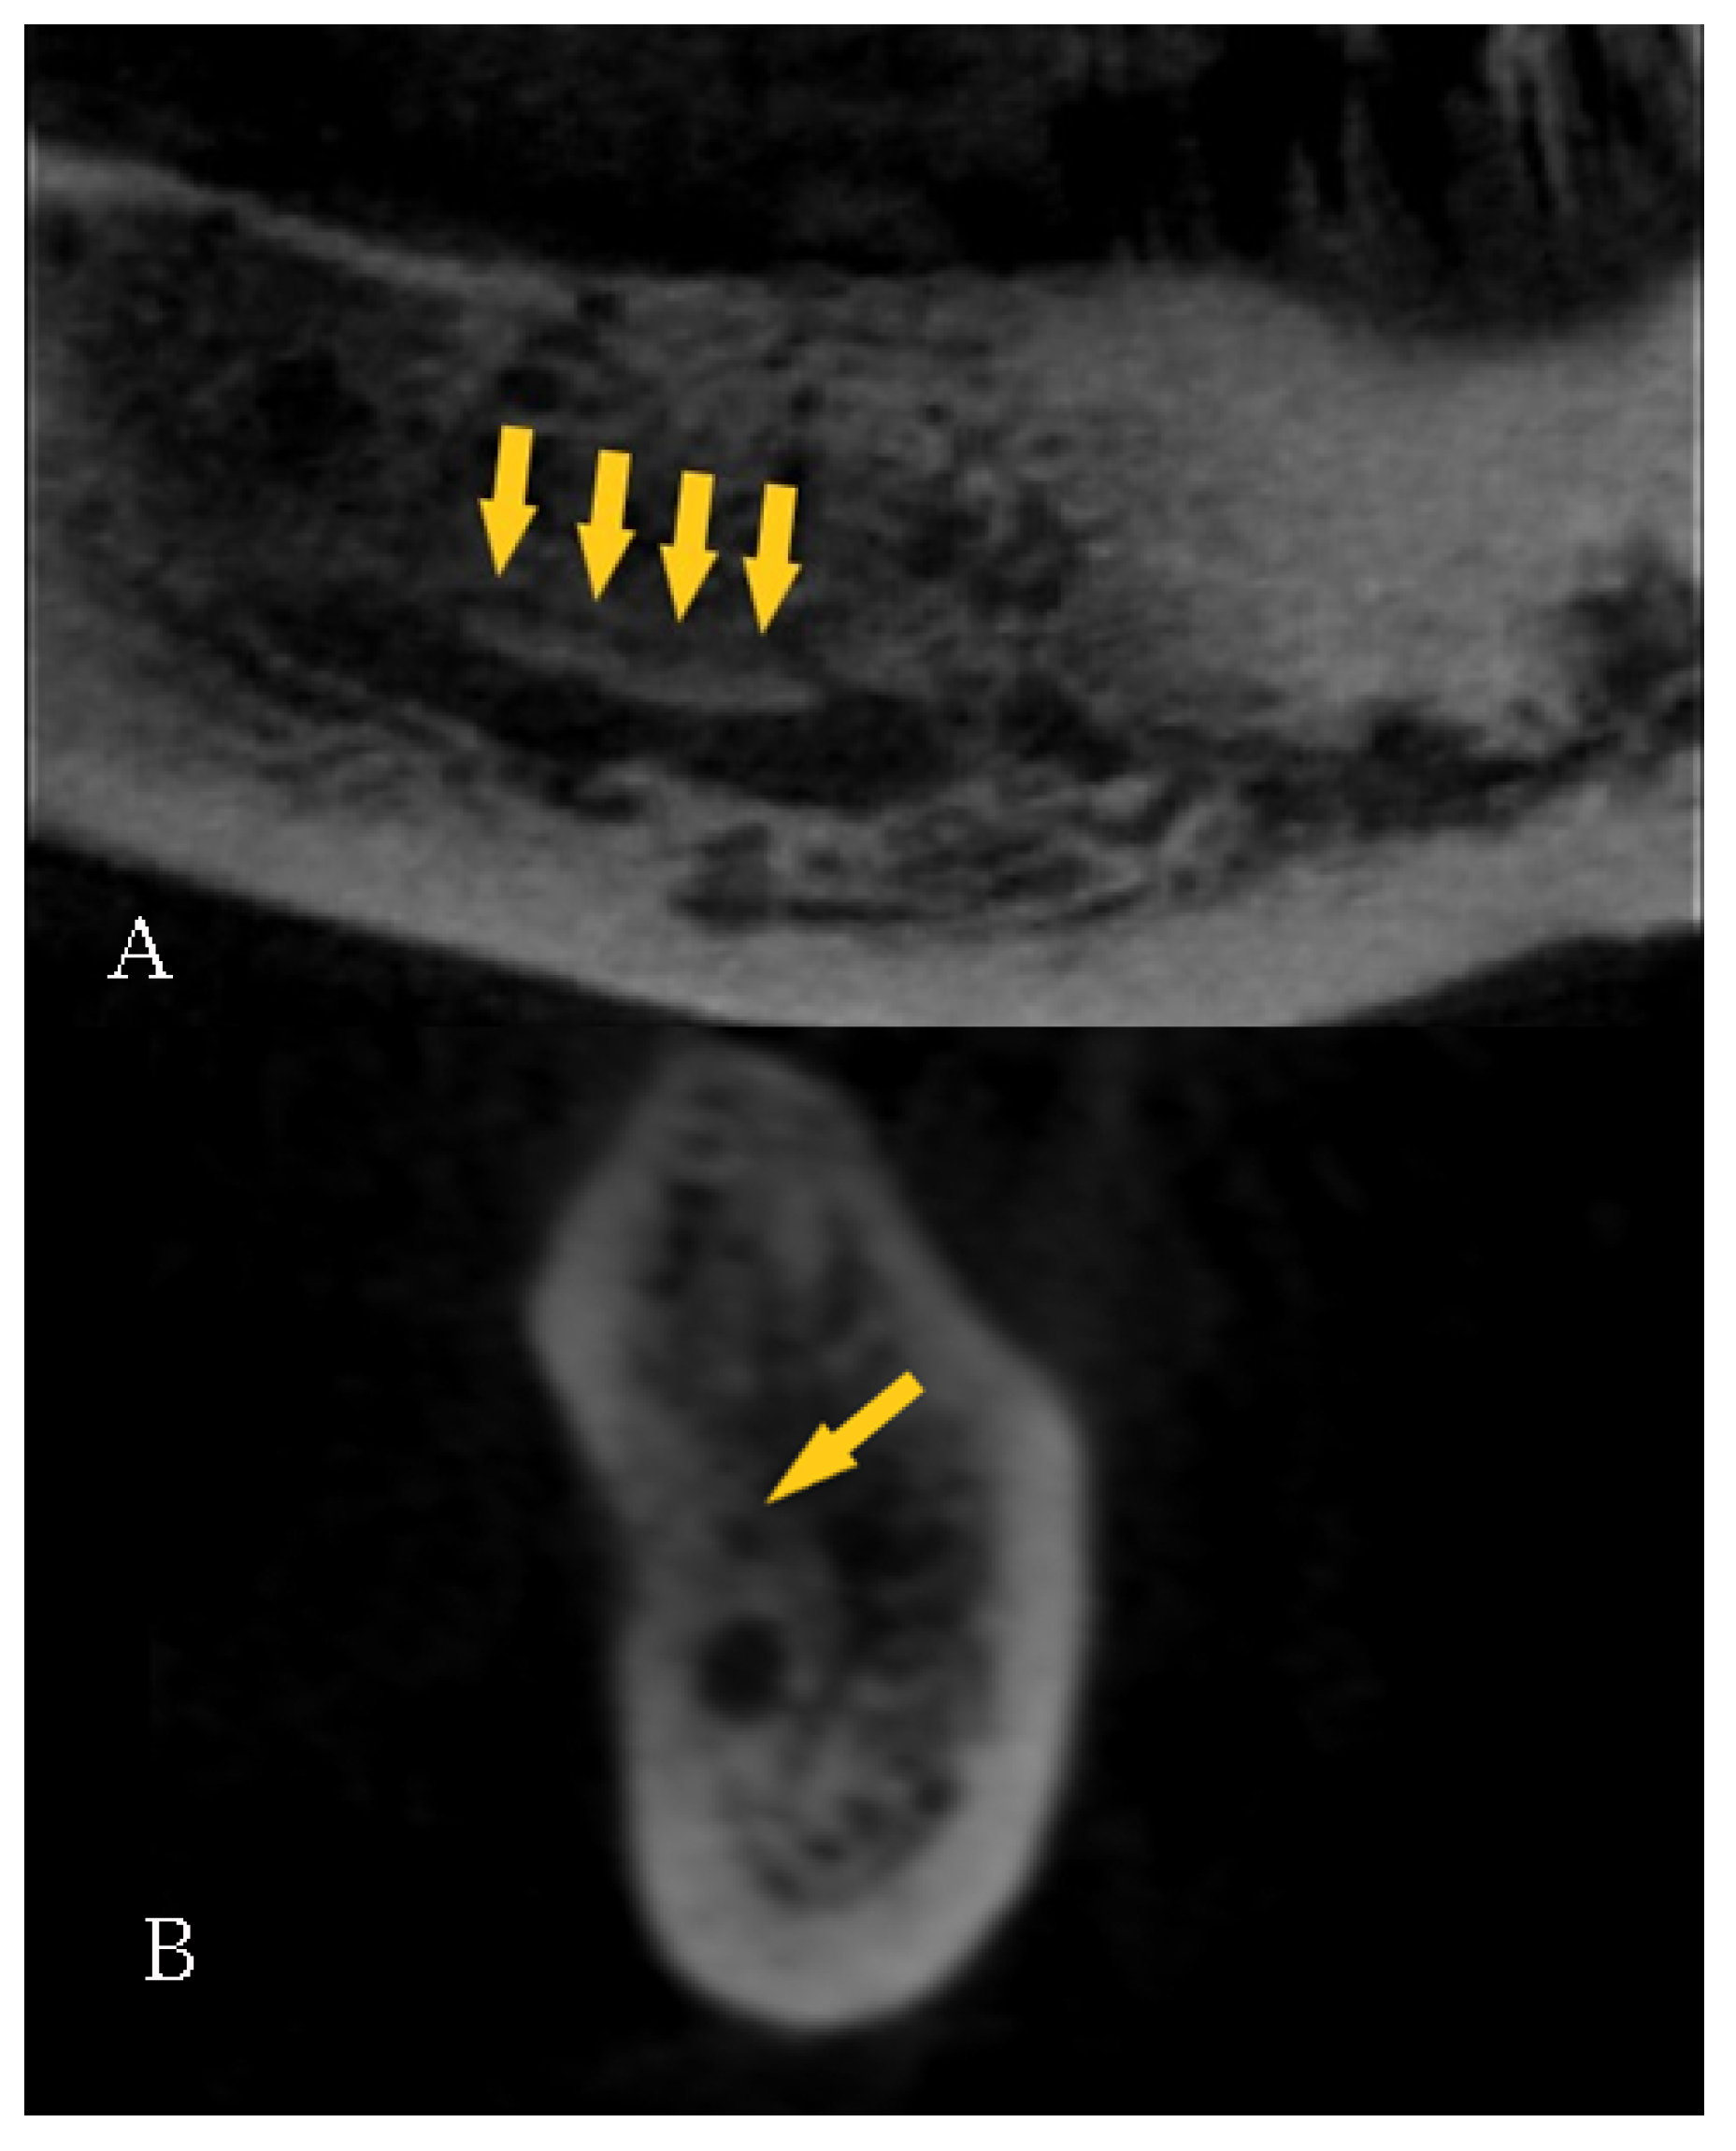

| Length right (mm) | 92 | 1.80 | 28.30 | 11.96 | 5.56 |

| Length left (mm) | 81 | 2.70 | 19.60 | 11.37 | 4.88 |